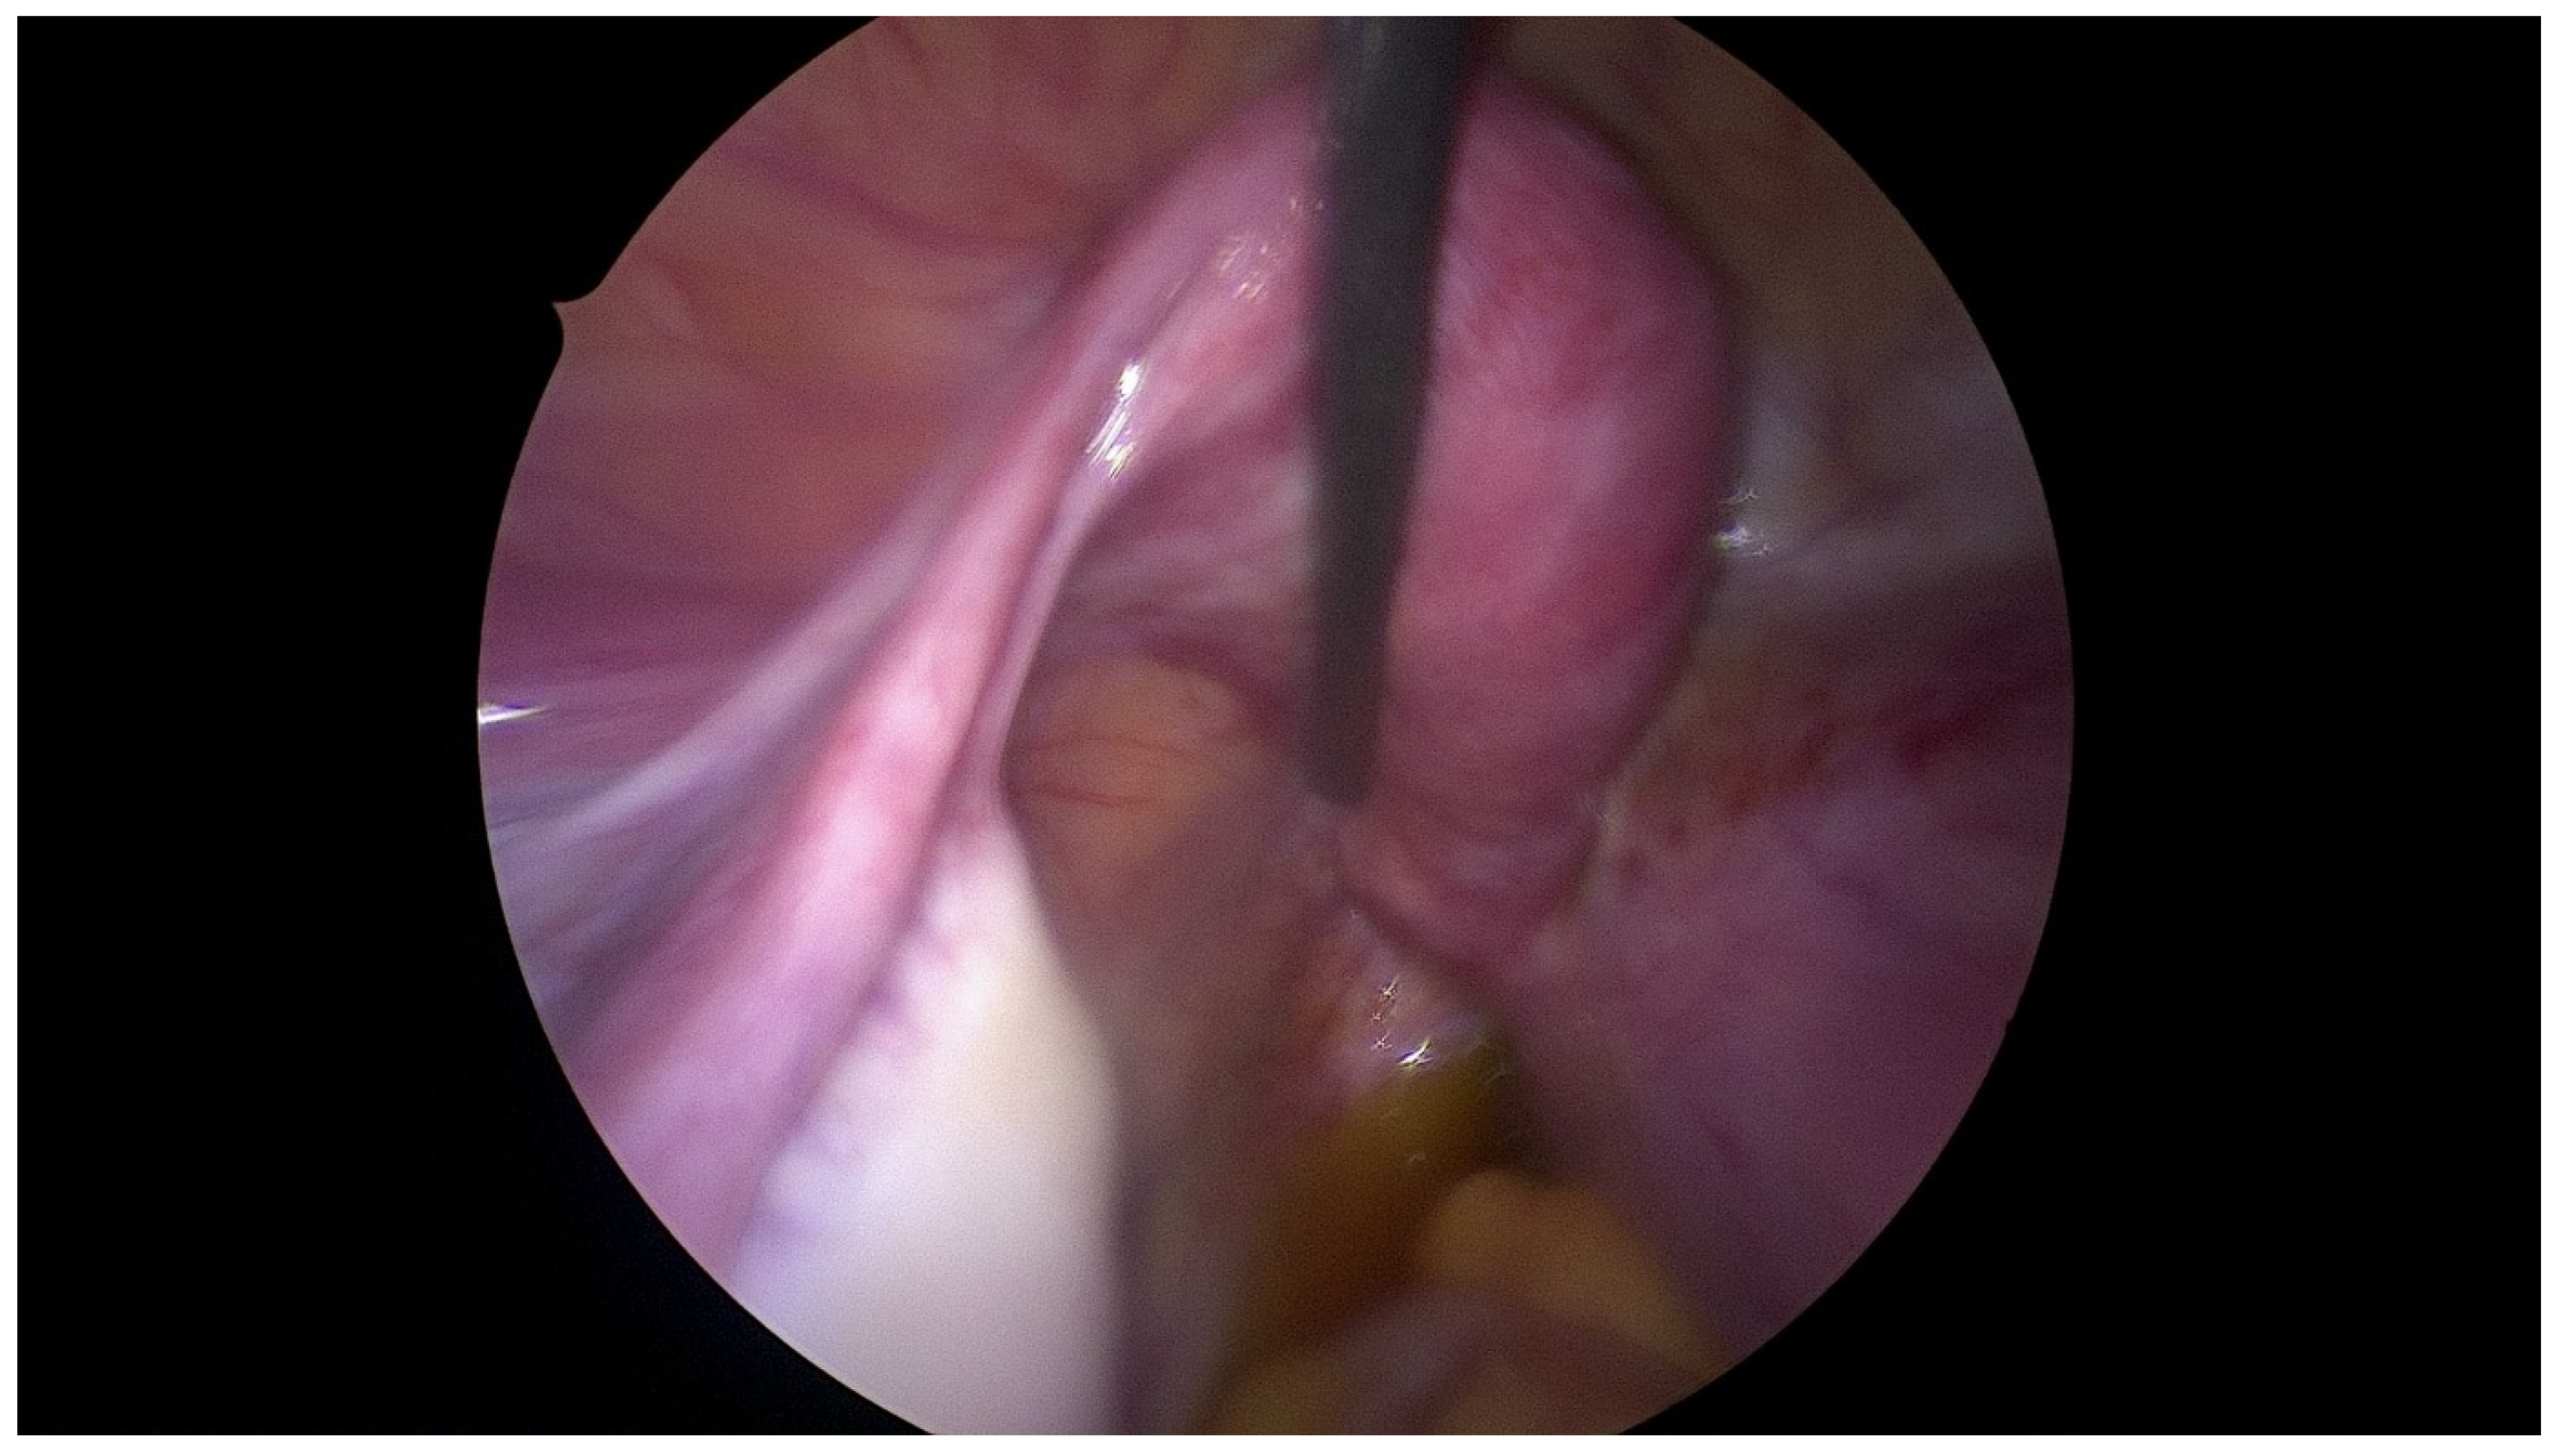

2.3. Surgical Technique

| Step 3. Surgical management Surgery is necessary when acute abdominal symptoms are present. “Wait and see” approach is only possible when the clinical situation allows it. Perform laparoscopy and vaginoscopy in order to achieve the correct diagnosis and treat concomitant hematosalpinx and endometriosis [14]. Intraoperative US is helpful to evaluate the place of resection. Unnecessary lengthening the time to diagnosis, contributes to unindentent consequence. |